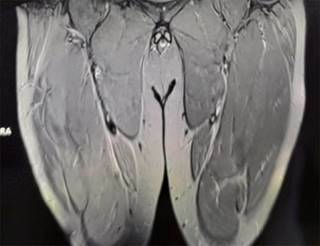

Figura 1: Imagen coronal de ambos muslos, potenciada en T2 con saturación espectral de grasa STIR, se muestra aumento de intensidad de forma difusa de ambos cuádriceps, siendo más importante en el derecho, lo que corresponde a edema muscular, con disrupción del trayecto de fibras del músculo recto anterior y vasto externo derechos.

Masculino de 42 años quien realizó ejercicio intenso por 80 minutos, 24 horas después presentó tumefacción dolorosa en cara anterior de ambos muslos, especialmente el derecho con aumento de volumen; incapacidad para la ambulación por dolor en muslos, además de orina oscura. Con diagnóstico presuncional de rabdomiólisis postejercicio. El laboratorio mostró: creatina cinasa (CPK) 11,000 U/L; transaminasa glutámico-oxalacética (TGO) 1,600 U/L; transaminasa glutámico-pirúvica (TGP) 280 U/L; el examen general de orina (EGO) oscura sin hematíes. La resonancia magnética (RM) mostró edema muscular de predominio derecho en cuádriceps y disrupción parcial de fibras del recto anterior (Figura 1).

La rabdomiólisis se caracteriza por necrosis de las células musculares, liberación de mioglobina, proteínas sarcoplásmicas y elevación de enzimas (CPK, LDH, TGO y TGP). En la patogenia indica lesión del sarcolema y/o depleción de adenosín trifosfato (ATP) en el miocito, destrucción muscular por aumento de calcio intracelular y contracción muscular persistente, disfunción mitocondrial, producción de radicales libres de oxígeno y activación de proteasas. La RM es de elección para diagnóstico, el edema es el patrón de anormalidad muscular observado con mayor intensidad de señal en imágenes potenciadas en T2 o STIR. El edema simétrico es típico de las miopatías inflamatorias y relacionadas con fármacos, el asimétrico corresponde a infección, radiación, mionecrosis y síndrome compartimental.